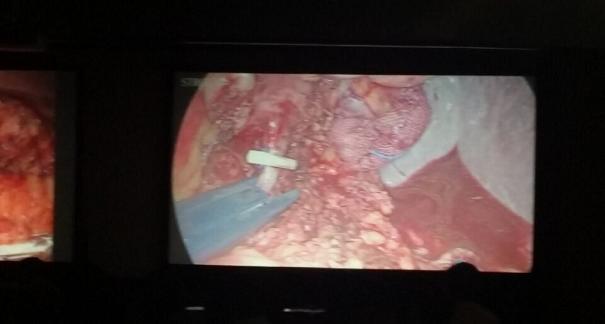

2015年10月23-25日,河北省醫(yī)學會肝膽外科學術年會在河北省石家莊市頤園賓館隆重召開。本次學術會議河北省醫(yī)學會特邀了北京301總院的胡明根教授、天津第一中心醫(yī)院的張雅敏教授、山西醫(yī)大醫(yī)院的趙浩亮、河北醫(yī)科大學第二醫(yī)院劉建華教授等國內知名專家參會。參加會議的醫(yī)院達100余家,近300名肝膽外科的臨床專家和一線醫(yī)生們親臨會場,在此進行廣泛的學術交流。25號全天會議安排了五臺手術視頻演示,全體參會人員進行觀摩,并實時提問,進行手術交流。演示手術包括腹腔鏡胰、十二指腸切除術、腹腔鏡左、右半肝切除術、腹腔鏡門脈高壓癥的治療、兩鏡或三鏡聯(lián)合膽石癥的治療、開腹胰、十二指腸切除術、手術演示中多次使用了我公司產品速豐(可吸收止血結扎夾),產品使用滿意度受到專家們的一致好評。